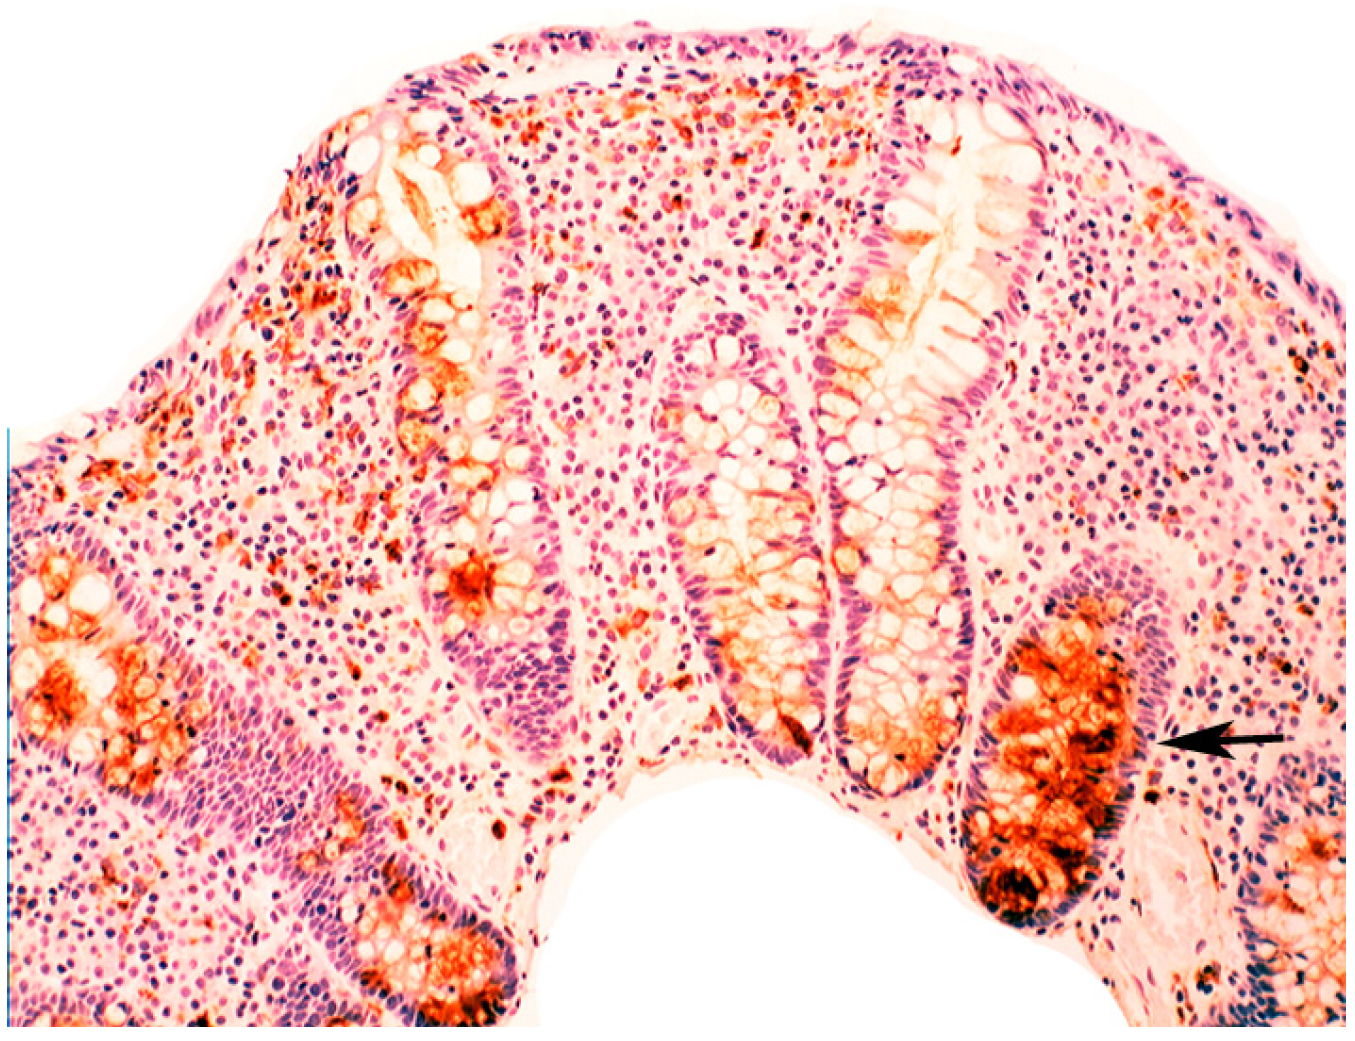

Figure 3. Close-up view of Barrett’s mucosa of intestinal phenotype, showing faintly stained goblet cells and at arrow, marked lysozyme expression in the secreted mucus, in the lumen of the gland (lysozyme immunostain, ×40).

When compared to controls, lysozyme was up-regulated in all three Barrett’s mucosal phenotypes [24]. In some goblet cells, lysozyme was slightly expressed. This phenomenon might be due to a prior goblet cells-discharge of lysozyme-rich intracellular mucus into the lumen (Figure 3). Lysozyme was not expressed in parietal (oxyntic) cells, neither in Barrett’s oesophagus (Figure 4), nor in controls [24].